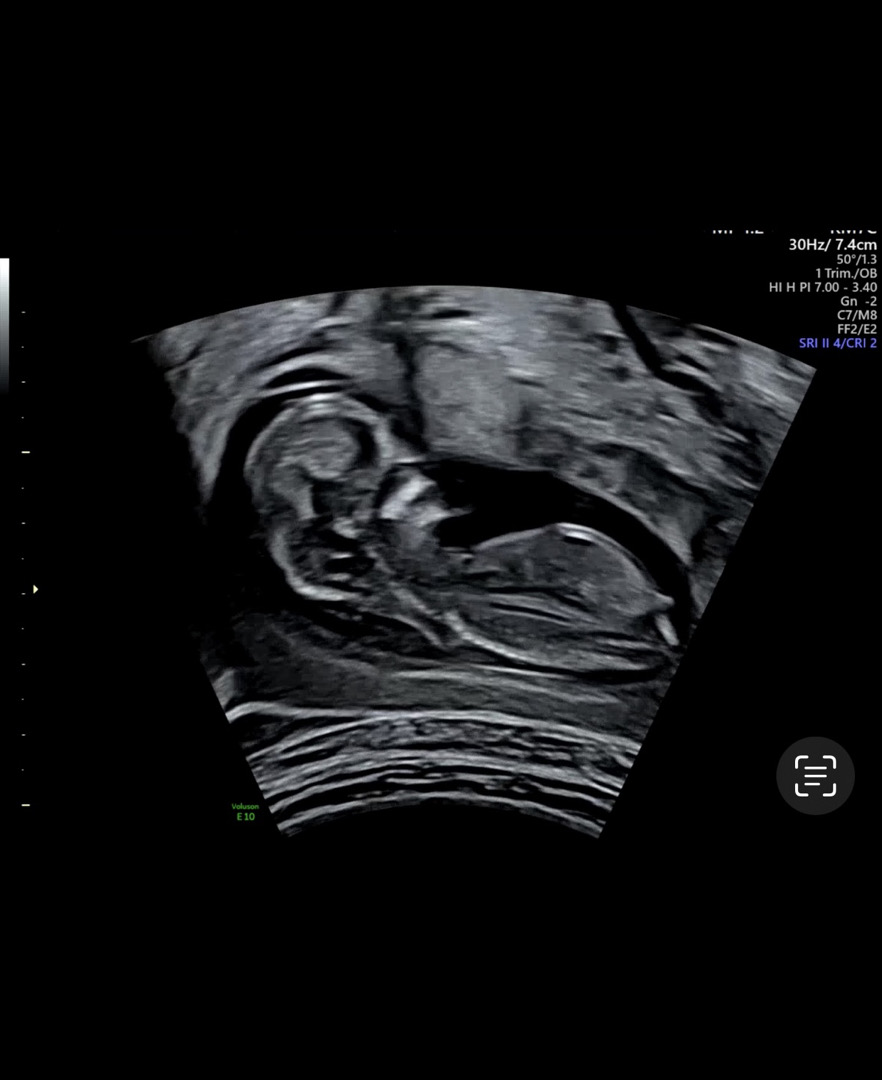

12주 5일 이구요~ 제가 초짜라 각도법이 뭔지 어떻게 보는 건지 모르겠어요🙏🏻 마구마구 참견 부탁해요